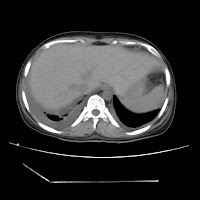

(HRCT)CT-Scan investigation done on 19Aug15 :

Series4